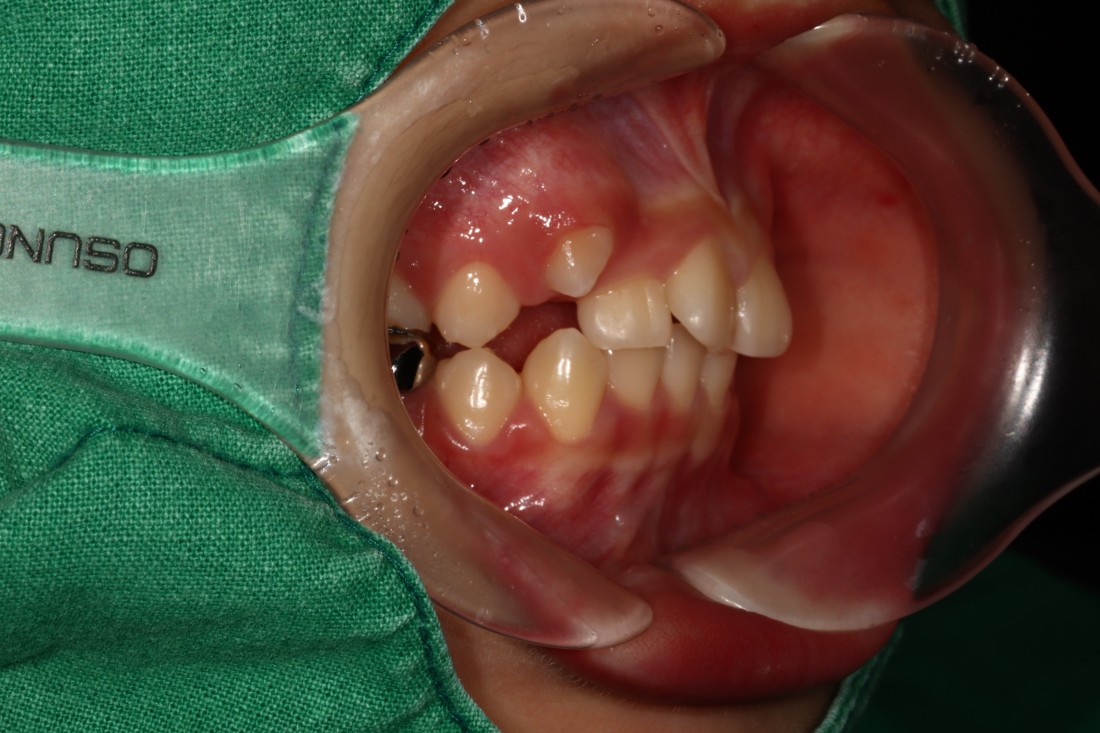

![]() | ![]() |

광주 덧니교정 치과는

대표원장인 제가 직접

다양한 교정 전/후 케이스를

공유하고 있습니다.

다양한 각도에서 촬영한

교정 전/후 사진을 직접 확인할 수 있어

광주 덧니교정 치과의

실력있는 진료를 증명하고 있습니다.

발치를 진행한 덧니교정이나

비발치 덧니교정 모두

다양한 케이스를 보유하고 있기 때문에

나의 구강구조와 비교해보면서

성공적인 교정치료 결과를

기대해보실 수 있습니다.